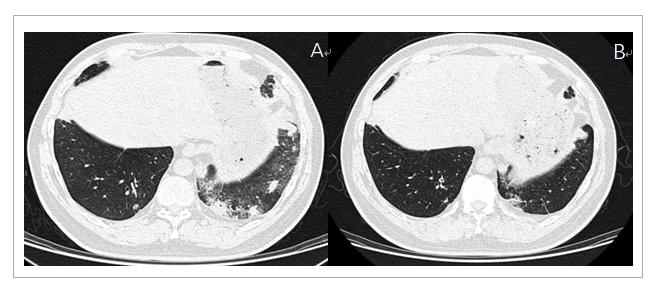

患者张某,男性,49岁,主因“间断左胸背痛伴左上肢麻木肿胀2个月”于2019年3月25日入院,入院查体神清,双肺呼吸音清,心、腹未见明显异常。实验室检查:血常规,肝肾功能基本正常,肿瘤标志物:细胞角蛋白19片段(Cyfra21-1) 6.42ug/L(正常0~3.3ug/L),其余肺部肿瘤标志物均在正常范围。行PET-CT:左肺尖可见软组织肿物影,密度欠均,CT值28-40Hu,增强后呈不均匀强化,CT值33-95Hu,边缘毛糙,牵拉临近胸膜,PET显像可见异常放射性农具,SUV值15.2,大小约5.1cm*4.1cm*4.1cm,周围可见多发斑片,条索及结节样影,考虑为周围性肺癌,临近胸膜受累。临床分期为T3N0M0,ⅡB期(图1A-B)于2019年4月4日进行CT引导下左肺上叶肿物穿刺,穿刺病理结果为:低分化非小细胞癌,结合免疫组化符合低分化鳞状细胞癌。免疫表型P40(+),CK5/6(-),CK7(+),TTF-1(-)。未见明显化疗禁忌症,分别于4月14日,5月8日,5月27日及6月19日分别行四周期新辅助化疗联合免疫治疗,具体用药方案为三周方案:紫杉醇(脂质体)270mg d1,卡铂600mg d1,纳武利尤单抗360mg d1。患者化疗反应不著,I度消化道反应及骨髓抑制。四周期治疗结束后肿瘤标志物Cyfra21-1降为3.31ug/L, 1周复查胸CT(28/6/19)提示:左肺上叶肿物较前缩小(3.6cm*2.5cm),其内实性成分略增大,疗效评价PR(图1C-F)。自第4周期新辅助治疗结束后患者逐渐出现咳嗽,胸闷,低热症状,胸CT提示双肺胸膜下多发实变浸润,考虑免疫性肺炎可能(图2A),予甲泼尼龙冲击(160mg/d)3天,而后逐渐减量至40mg,共2周,同时予头孢哌酮舒巴坦对症治疗,2周后改为泼尼松15mg口服,患者症状明显好转,复查胸CT左下肺斑片影较前吸收(图2B)。后患者充分评估后于2019年10月17日行达芬奇机器人辅助下胸腔镜左上肺切除+区域淋巴结清扫术,手术过程顺利,术中未见明显胸膜受侵,术后病理提示:左上肺低分化癌,结合免疫组化考虑大细胞癌伴鳞状细胞癌分化,并伴大量坏死,送检壁层胸膜(-),区域淋巴结未见癌转移,病理分期T2bN0M0ⅡA期。术后患者恢复良好,后患者先后行3周期术后辅助化疗,三周方案,具体为紫杉醇(脂质体)240mg d1,卡铂500mg d1。目前定期复查密切随诊,状态良好,无复发及转移征象。

图2 (A). 28/6/19胸CT提示右下肺出现免疫性肺炎;(B). 24/7/19胸CT提示经激素冲击治疗后肺部浸润实变情况明显改善。